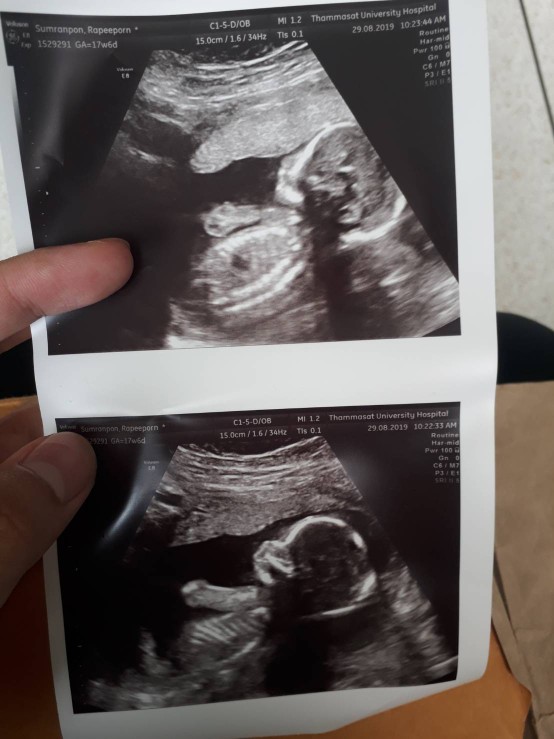

บ้านนี้ตอนประมาณ20w